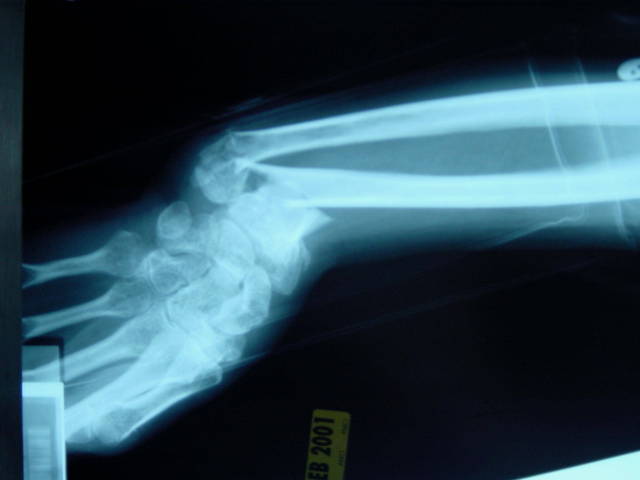

• broken wrist

broken wrist

i was skating down my street and fell and broke my hand my wrist has never been the same since